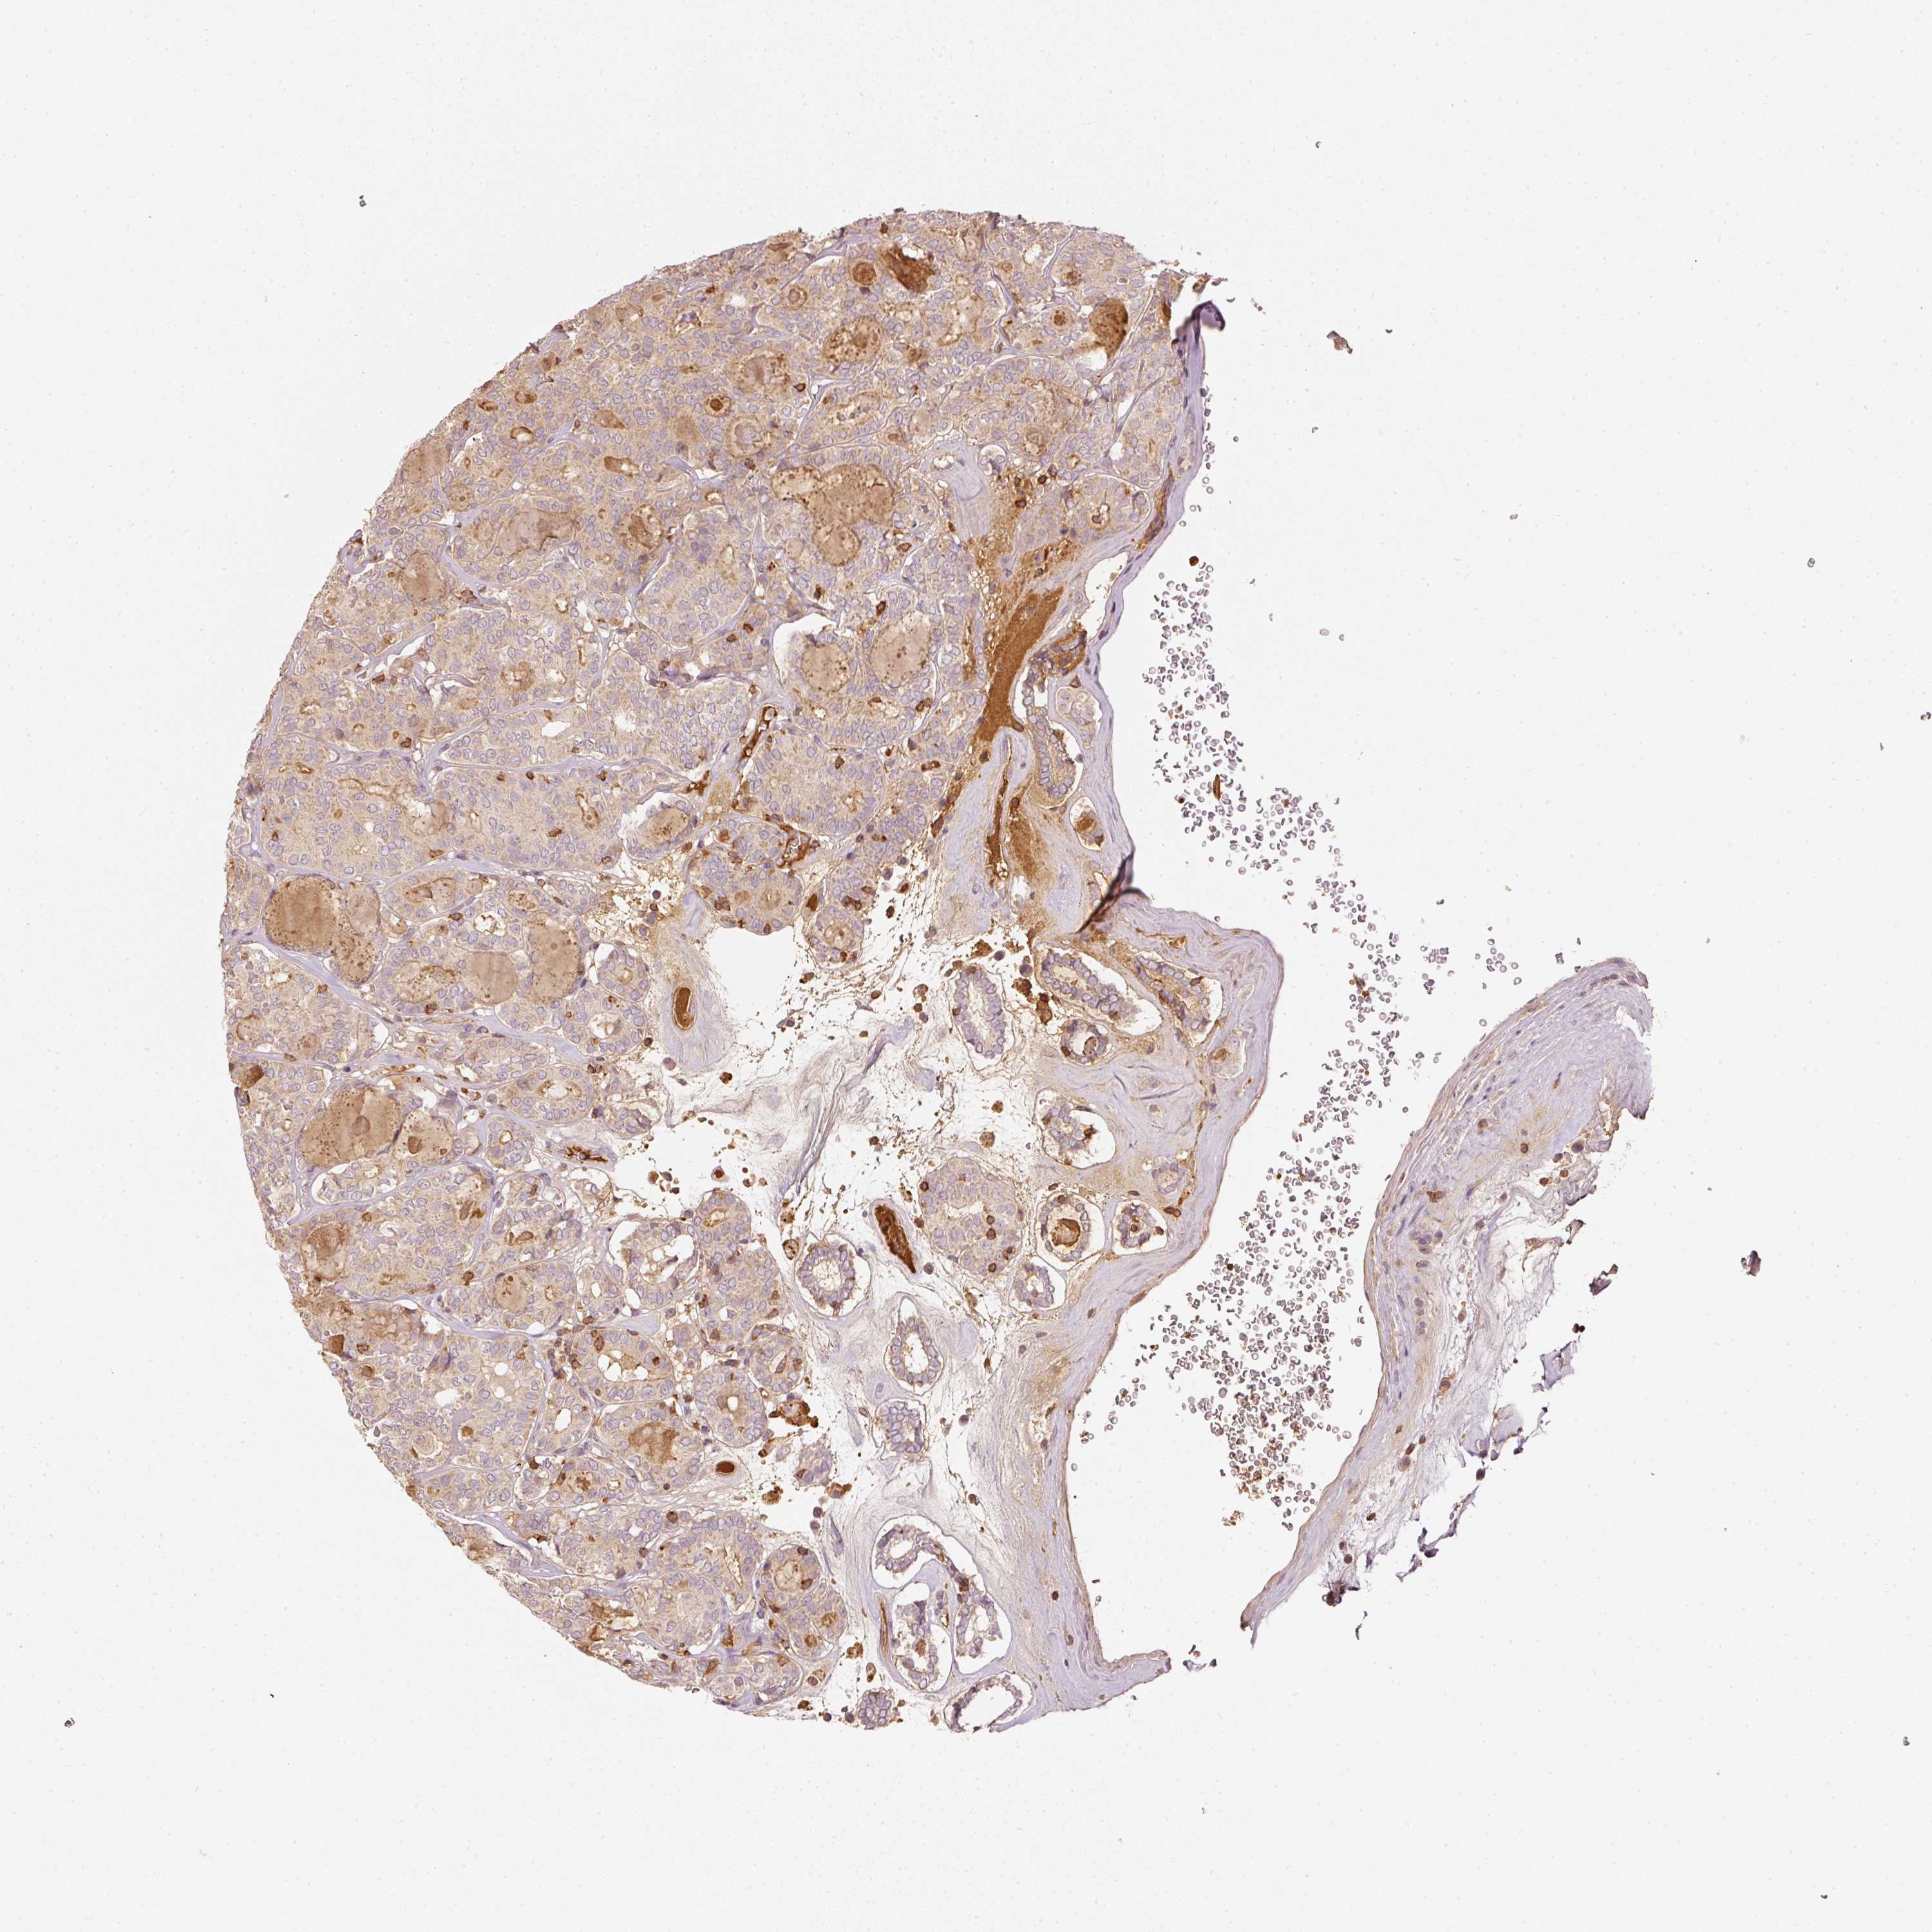

THYROID CANCER - Protein expressioni

A mouse-over function shows sample information and annotation data. Click on an image to view it in a full screen mode. Samples can be filtered based on level of antibody staining by selecting one or several of the following categories: high, medium, low and not detected. The assay and annotation is described here.

Note that samples used for immunohistochemistry by the Human Protein Atlas do not correspond to samples in the TCGA dataset.

Antibody stainingi

Antibody staining in the annotated cell types in the current human tissue is reported as not detected, low, medium, or high, based on conventional immunohistochemistry profiling in selected tissues. This score is based on the combination of the staining intensity and fraction of stained cells.

Each image is clickable and will lead to virtual microscopy that enables deeper exploration of all samples and also displays staining intensity scores, fraction scores and subcellular localization as well as patient and tissue information for each sample.

Antibody HPA018849

Antibody HPA019536

Antibody CAB033987

Staining

High

Medium

Low

Not detected

Intensity

Strong

Moderate

Weak

Negative

Quantity

>75%

75%-25%

<25%

None

Location

Nuclear

Cytoplasmic/membranous

Cytoplasmic/membranous,nuclear

Papillary adenocarcinoma, NOS

Follicular adenoma carcinoma, NOS